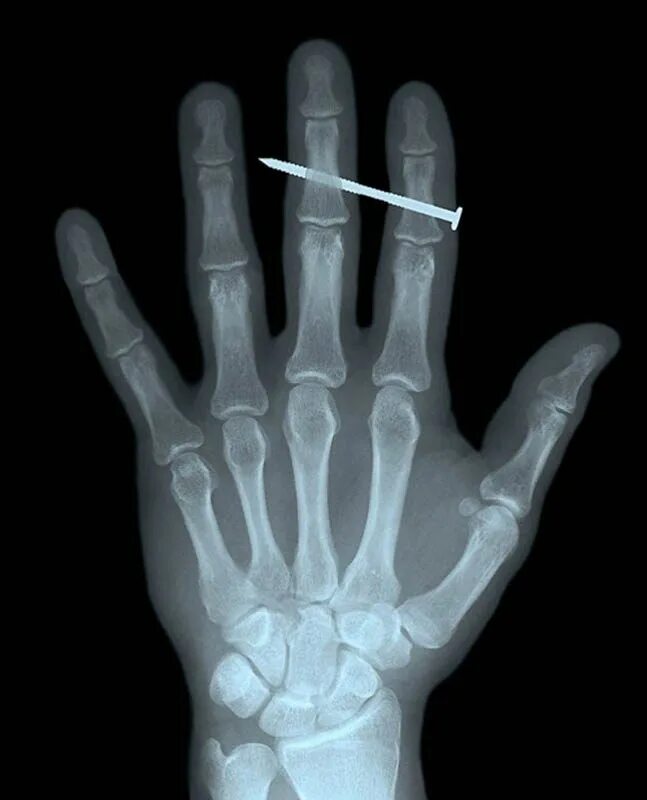

Рентген делают в одежде или нет